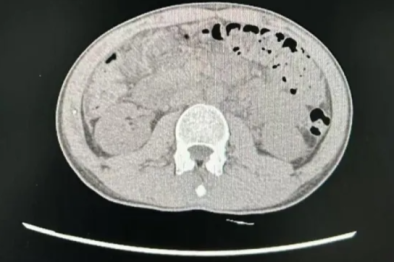

武汉大学人民医院一周成功救治 2 例肝癌破裂出血高危患者